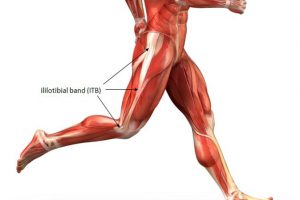

例えば、呼吸の仕方を変えたり、肩の動かし方を変えたり、腰の使い方を変えるだけで、ひざの痛み以外にも、腰などの関節のお悩みが改善されます。

さらにお伝えすると、同じひざの痛みだとしても、原因は先ほどお伝えしたように「一人一人必要な運動方法が違う」という事です。